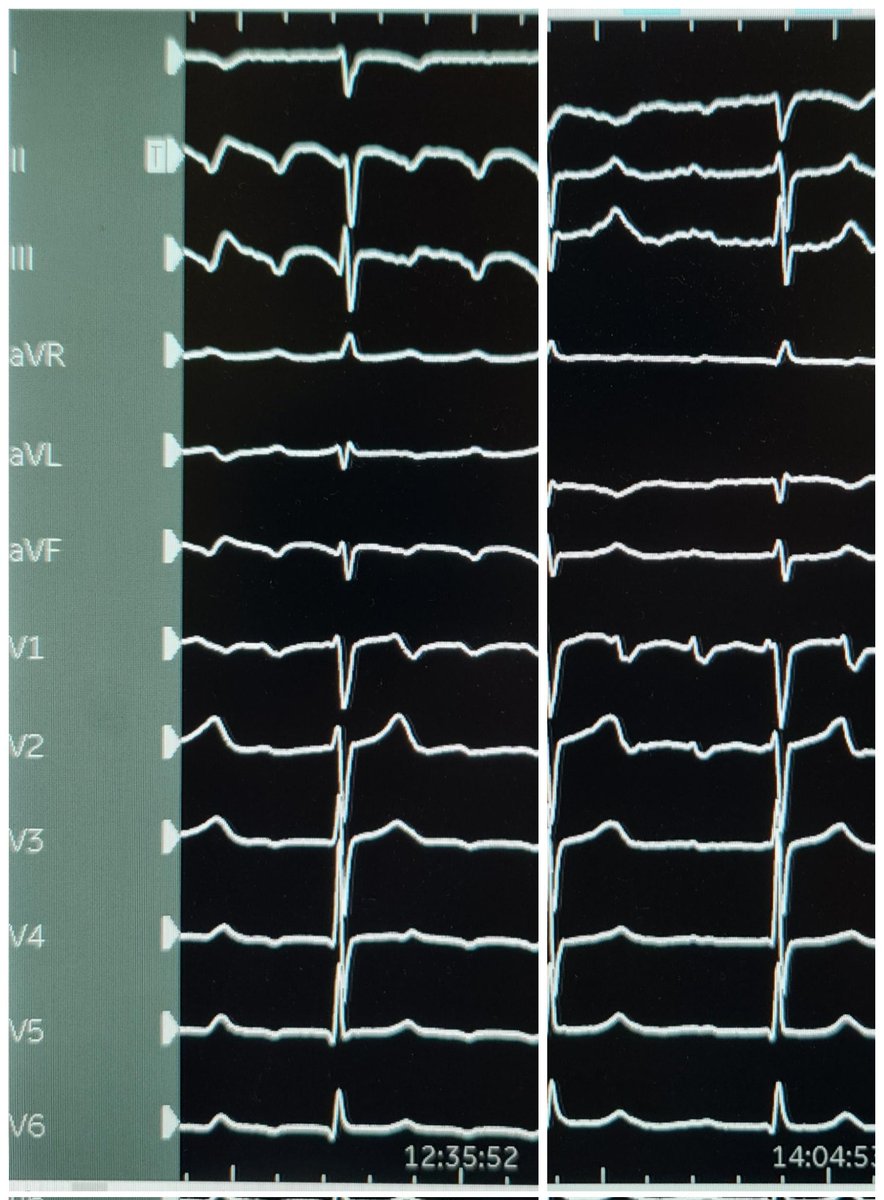

(2) Initial flutter morphology suggested counterclockwise CTI dependant flutter but morphology changed during mapping.

(1) Ablation of atriotomy-related atrial flutter in patient with AVR / root 12 yrs ago. CARTO activation / propagation showing counterclockwise pivot around scar. @FeatonbyLuke @biosensewebster @sjoshi_23 #epeeps #coherent #RieCathLab #cardiotwitter #EHRA #BHRS